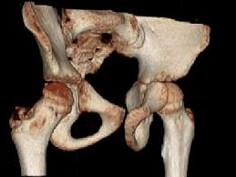

问题 男,13岁,右髋部疼痛不适,无红肿,请结合所提供的图像,选择最佳答案 ( )

选项 A、内生软骨瘤 B、骨纤维结构不良 C、骨巨细胞瘤 D、畸形性骨炎 E、非骨化性纤维瘤

答案 B